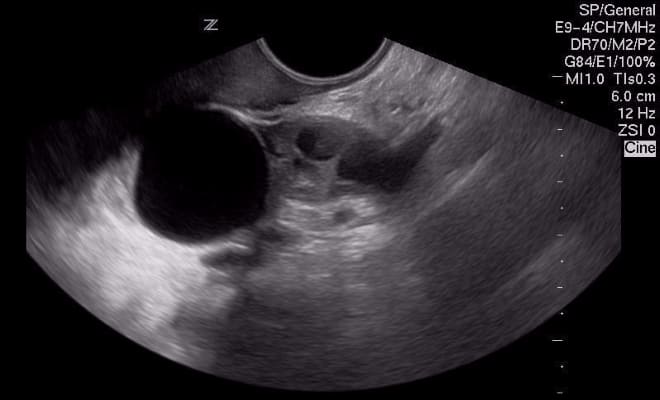

Поликистоз

При наличии синдрома поликистозных яичников (СПКЯ) ультразвуковое исследование позволяет выявить как минимум 10 фолликулов, которые располагаются в виде ожерелья из жемчуга.

В случае развития данной патологии парные половые железы увеличиваются в объеме. УЗИ у пациенток с поликистозом показывает наличие не менее 10 патологических образований в придатках, каждое из которых достигает размера 1 см.